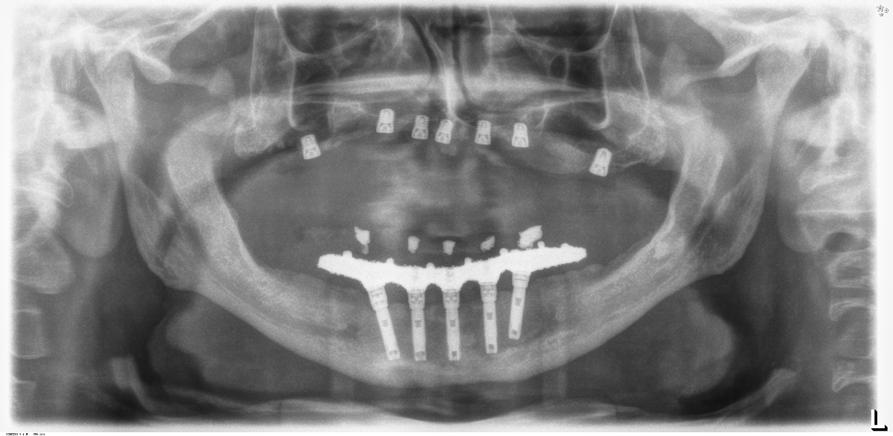

En el maxilar superior, existen trabajos de revisión donde se pone de manifiesto que los implantes cortos y extracortos tienen también un correcto comportamiento biomecánico y pérdidas óseas similares a los implantes de mayor longitud, por lo que para esta área anatómica también son una opción de tratamiento predecible.1,12 En la siguiente serie de casos clínicos, presentamos 5 pacientes en los que se han realizado rehabilitaciones sobre implantes extracortos 5.5 mm para generar prótesis de arco completo, en maxilar y mandíbula y su seguimiento a lo largo del tiempo observándose la supervivencia de los implantes, la pérdida ósea crestal con la función y las posibles complicaciones protésicas acontecidas durante el tiempo de seguimiento.

Figura 2 y 3. Figuras intraorales del paciente de 67 años que acude a la consulta para rehabilitación sobre implantes superior, portador de una prótesis completa removible con una atrofia ósea evidente al ser la prótesis retirada. Figura 4. La radiografía inicial muestra una atrofia marcada en sentido vertical, que debe ser constatada posteriormente mediante un TAC así como para la planificación de la colocación de los implantes. Figura 5 y 6. Encerado diagnóstico para comenzar la planificación de la colocación de los implantes superiores guiados por la posición ideal que deben tener los dientes en la prótesis. De este encerado se realiza una guía radiológica que nos permita trasladar estas posiciones al TAC de planificación.

Fueron reclutados 6 pacientes en los que se colocaron 30 implantes para realizar rehabilitaciones completas. La edad media de los pacientes incluidos en el estudio fue de 66.75 años (+/- 5,16) y un 86.7% fueron mujeres. El 63.3% de los implantes se insertaron en el maxilar superior y el 36.7% restante en la mandíbula, formando parte de 4 rehabilitaciones

completas superiores y 3 inferiores. Todos los implantes presentaron una longitud de 5.5 m m, con diámetros comprendidos entre los 2.5 y los 5.5 mm. Las posiciones de los implantes corresponden a distribuciones biomecánicas para la realización de prótesis completas tanto en el maxilar como mandíbula (incisivos, premolares y molares). Los diámetros y longitudes de los implantes incluidos en el estudio en función de

181. Septiembre 2023 51 Rehabilitaciones completas implantosoportadas

su posición se muestran en la Figura 1.

Figura 7­9. Cortes de planificación del cone beam donde observamos la extrema atrofia vertical y la posición en la que deberían situarse los dientes con una gran discrepancia entre esta posición y la base ósea. Vemos también como se planifican implantes extracortos de 5.5 mm de longitud en todas las localizaciones. Figura 10. Radiografía panorámica tras la colocación de los implantes.

En las Figuras 2­17 se puede observar uno de los casos incluidos en el estudio.